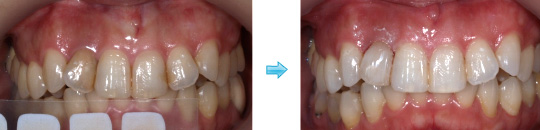

ホワイトニング症例

ホームホワイトニング

オフィスホワイト二ング